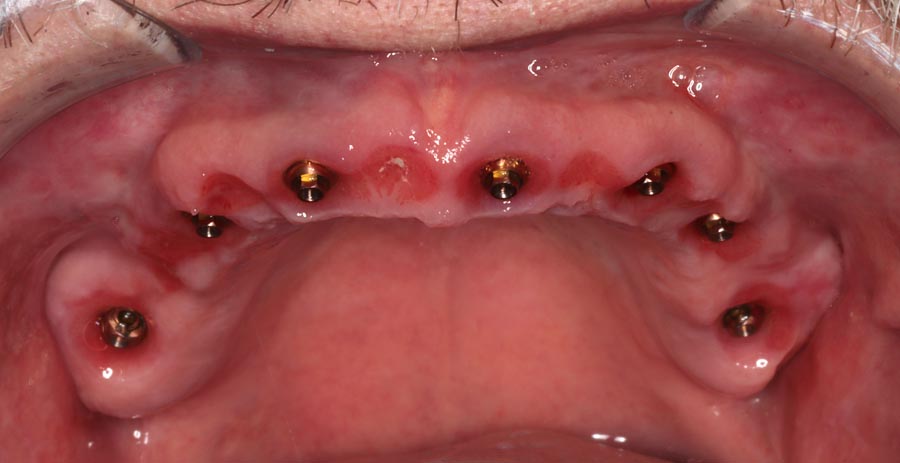

Smile GalleryImplant RestorationsFull Mouth Implant Restoration 1 of 13 Pre-operative smile Pre-operative smile Pre-operative frontal view, lips retracted Pre-operative panoramic image (note bone levels) Post-surgical panoramic image Surgical temporary bridge (note convex contours) Delivery of surgical temporary bridges in both upper and lower Two weeks post-op surgery and temporaries (note amazing tissue response) Three months post- surgery. (Note tissue development) Definitive implant bridges (FP-2) Post-treatment panoramic image Final result smile Final result smile